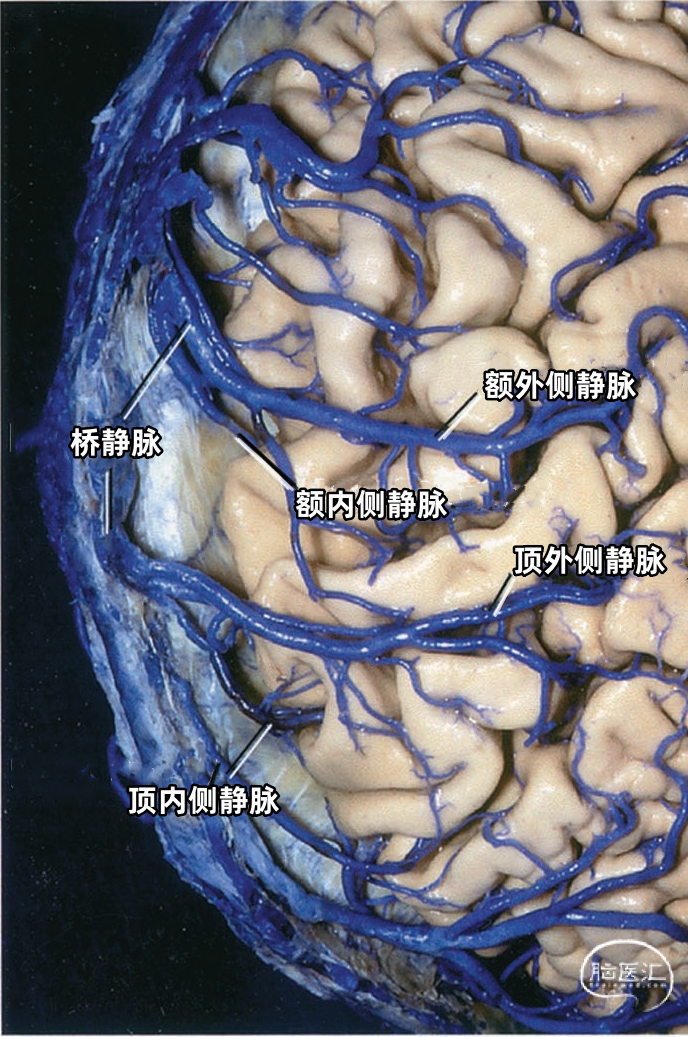

下图示切除静脉腔隙,显示上矢状窦右侧面。可见静脉在静脉腔隙下方进入上矢状窦。额内侧静脉、额外侧静脉以及顶内侧静脉、顶外侧静脉经常在入窦前汇合成共干,然后进入上矢状窦。

多数皮层静脉由单根起始,逐渐接受属支。相邻区域的皮层静脉可汇合成为一支桥静脉,穿出蛛网膜下腔,最后汇入硬膜窦。另外,引流半球内侧、外侧和底面的静脉,可能在交界区形成为一支桥静脉,最后汇入一个静脉窦。大脑内侧和外侧的上升静脉经常在半球上缘汇合,并进入上矢状窦;半球外侧下降的引流静脉和半球底面向外的引流静脉可在半球下缘汇合,进入颅底的硬膜窦。少数皮层静脉加入脑深部静脉系统。 相邻区域的血管间有互补关系,即某一静脉引流的区域增多,则相邻静脉的引流范围随之减少。在脑叶或面的主要引流静脉组之间也有类似的互补关系。

▼1.额叶

▼2.顶叶

上矢状窦组(上图 深蓝色)由回流至上矢状窦的静脉组成,包括引流额叶、顶叶、枕叶内侧、外侧面上部皮层以及额叶眶面前部的静脉。 注入上矢状窦的大脑外侧面静脉包括额极静脉、额前静脉,额中静脉、额后静脉,中央前静脉、中央静脉、顶前静脉、顶后静脉、枕静脉和Trolard静脉。 注入上矢状窦的大脑内侧面静脉(上图 蓝色)包括额前内侧静脉,额中内侧静脉、额后内侧静脉、旁中央沟静脉、顶前内侧静脉、顶后内侧静脉和距状后静脉。 一般静脉在离开软膜-蛛网膜注入上矢状窦前,会在硬膜下腔有1~2cm长的游离段。这些静脉可能直接汇入上矢状窦,也可能先汇入硬膜内的硬膜窦,再进入上矢状窦。